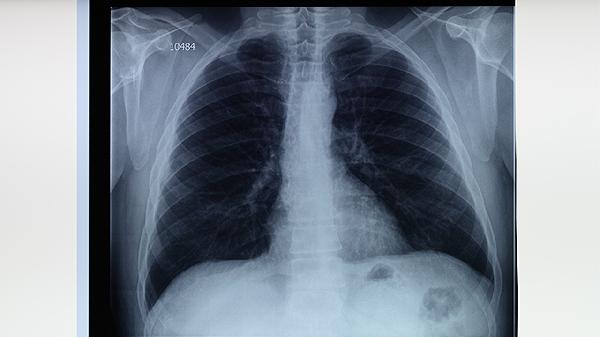

肺结核是由结核分枝杆菌引起的慢性传染病,体检是否过关主要取决于疾病状态。若处于活动期,痰涂片或培养阳性、胸部影像学显示浸润性病灶且伴有咳嗽发热等症状时,具有较强传染性,此时体检通常无法通过。我国传染病防治法将活动性肺结核列为乙类传染病,相关行业入职体检明确要求排除传染风险。部分特殊职业如食品加工、幼教、医疗等岗位的体检标准更为严格。

经规范抗结核治疗完成疗程,痰菌转阴6个月以上,胸片显示病灶稳定钙化,经专科医生开具治愈证明后,体检可通过审核。非活动性肺结核或陈旧性病灶若无传染性,一般不影响体检结果。部分单位可能要求提供疾病史说明或复查痰检报告,但通常不作为淘汰依据。境外部分国家移民体检时,对既往肺结核病史者需额外提交痰培养及治疗记录。